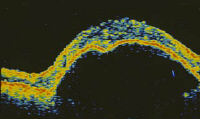

1. Match the OCT (optical coherence topography a-d ) with the most likely options

(A-N) listed below:

A. macular oedema

B. macular pucker

C. macular pseudohole

D. stage 1 macular hole

E.  stage 2 macular hole

F.  stage 3 macular hole

G. stage 4 macular hole

H. angioma

I.  macular drusen

J.  choroidal naevus

K. subhyaloid haemorrhage

L.  vitreous haemorrhage

M. pigment epithelium detachment

N.  retinoschisis

b.